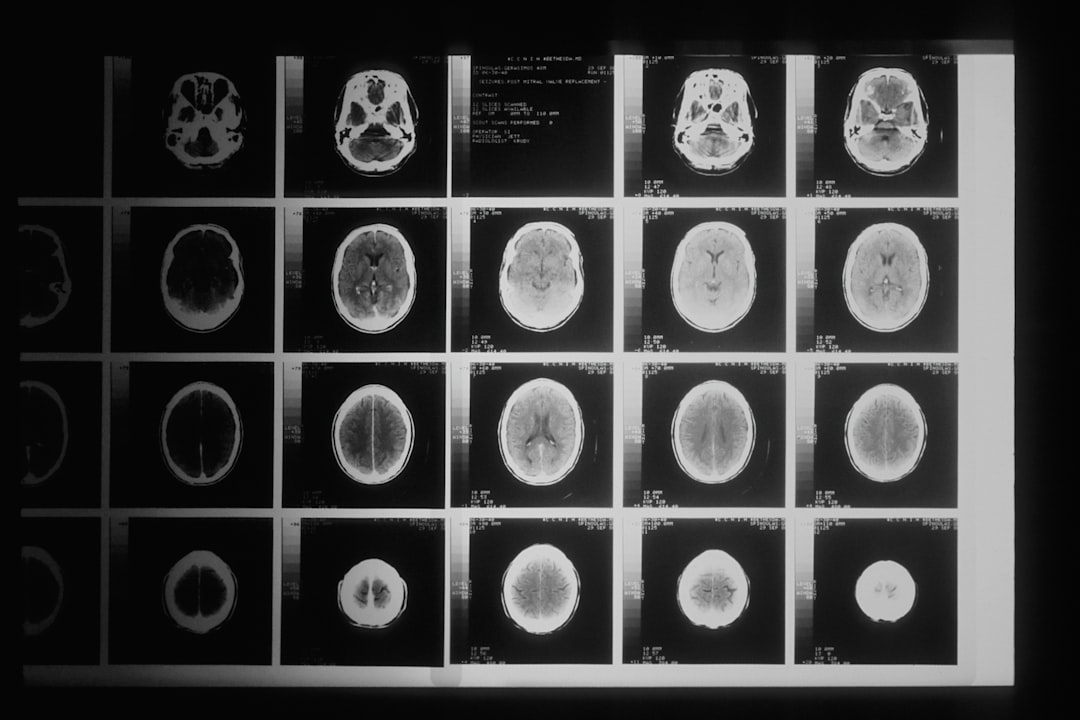

CT 검사는 컴퓨터 단층촬영의 약자로, 고해상도의 이미지를 가져오기 위해 여러 각도의 X선 이미지를 결합하는 방법입니다. 이를 통해 신체 내부의 구조를 매우 명확히 볼 수 있습니다. CT 검사는 질병을 진단하고 치료 계획을 세우는 데 매우 유용한 도구입니다. 종류는 다양하며 폐 CT 검사 비용처럼 특정 부위의 검사 비용이 다릅니다. 검사 전 상담을 통해 어떤 검사가 필요한지 전문가와 상의하는 것이 중요합니다.

검사 후, 의사는 촬영된 이미지를 분석하여 진단을 내립니다. 어떤 문제인지, 상태가 어떤지에 대한 정보가 동시에 제공되기 때문입니다. CT 검사 결과에 따라 추가적인 치료방법이나 관리 방안이 수립되기도 합니다. 뇌 CT 검사 비용과 같은 뇌 관련 검사도 필수적인 경우가 많아 많은 사람들이 이를 고려하고 있습니다.